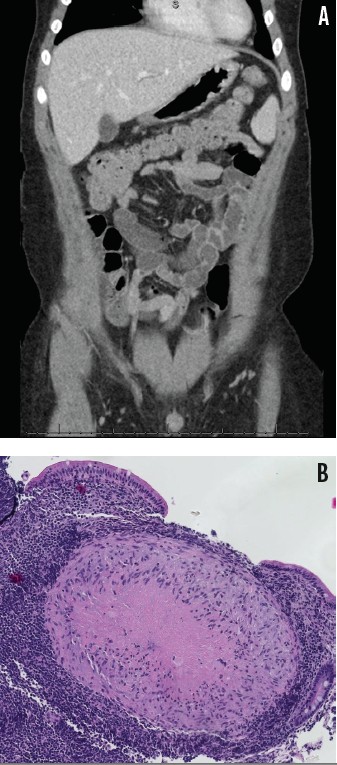

Roberto P. Santos, MD; Monica Liao Chang, MD; Maria Kristina Subik, MD

A previously healthy 11-year-old boy presented with a 6-week history of fever and abdominal pain with alternating diarrhea and constipation. He had no sick contacts, recent travel history, or household...